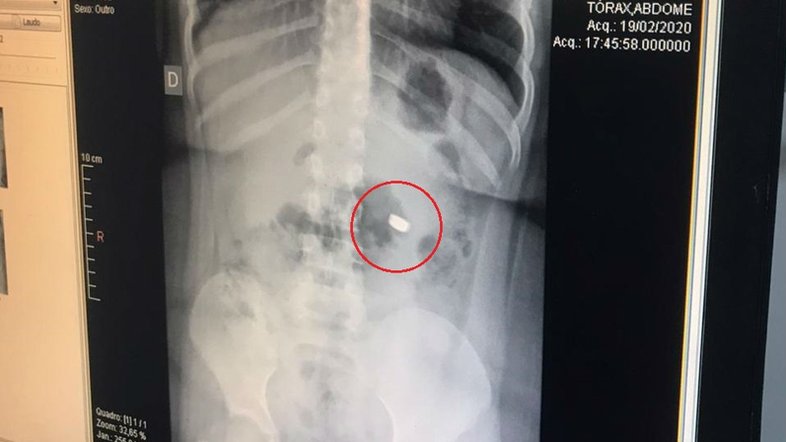

Na manhã desta sexta-feira (21), exames de raio-x constataram que a bateria tinha saído do estômago e seguido para o intestino. Por isso, a equipe médica optou pelo expelimento nas fezes. Apesar do susto, a criança passa bem e o objeto foi expelido naturalmente.